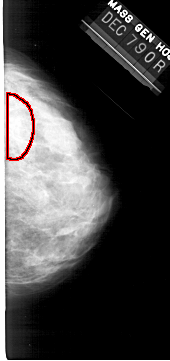

A_1364_1.RIGHT_CC

RIGHT_CC LINES 5041 PIXELS_PER_LINE 2371 BITS_PER_PIXEL 12 RESOLUTION 43.5 OVERLAY

FILE: A_1364_1.RIGHT_MLO.OVERLAY

TOTAL_ABNORMALITIES 1

ABNORMALITY 1

LESION_TYPE CALCIFICATION TYPE AMORPHOUS DISTRIBUTION SEGMENTAL

ASSESSMENT 4

SUBTLETY 3

PATHOLOGY BENIGN

TOTAL_OUTLINES 1

BOUNDARY